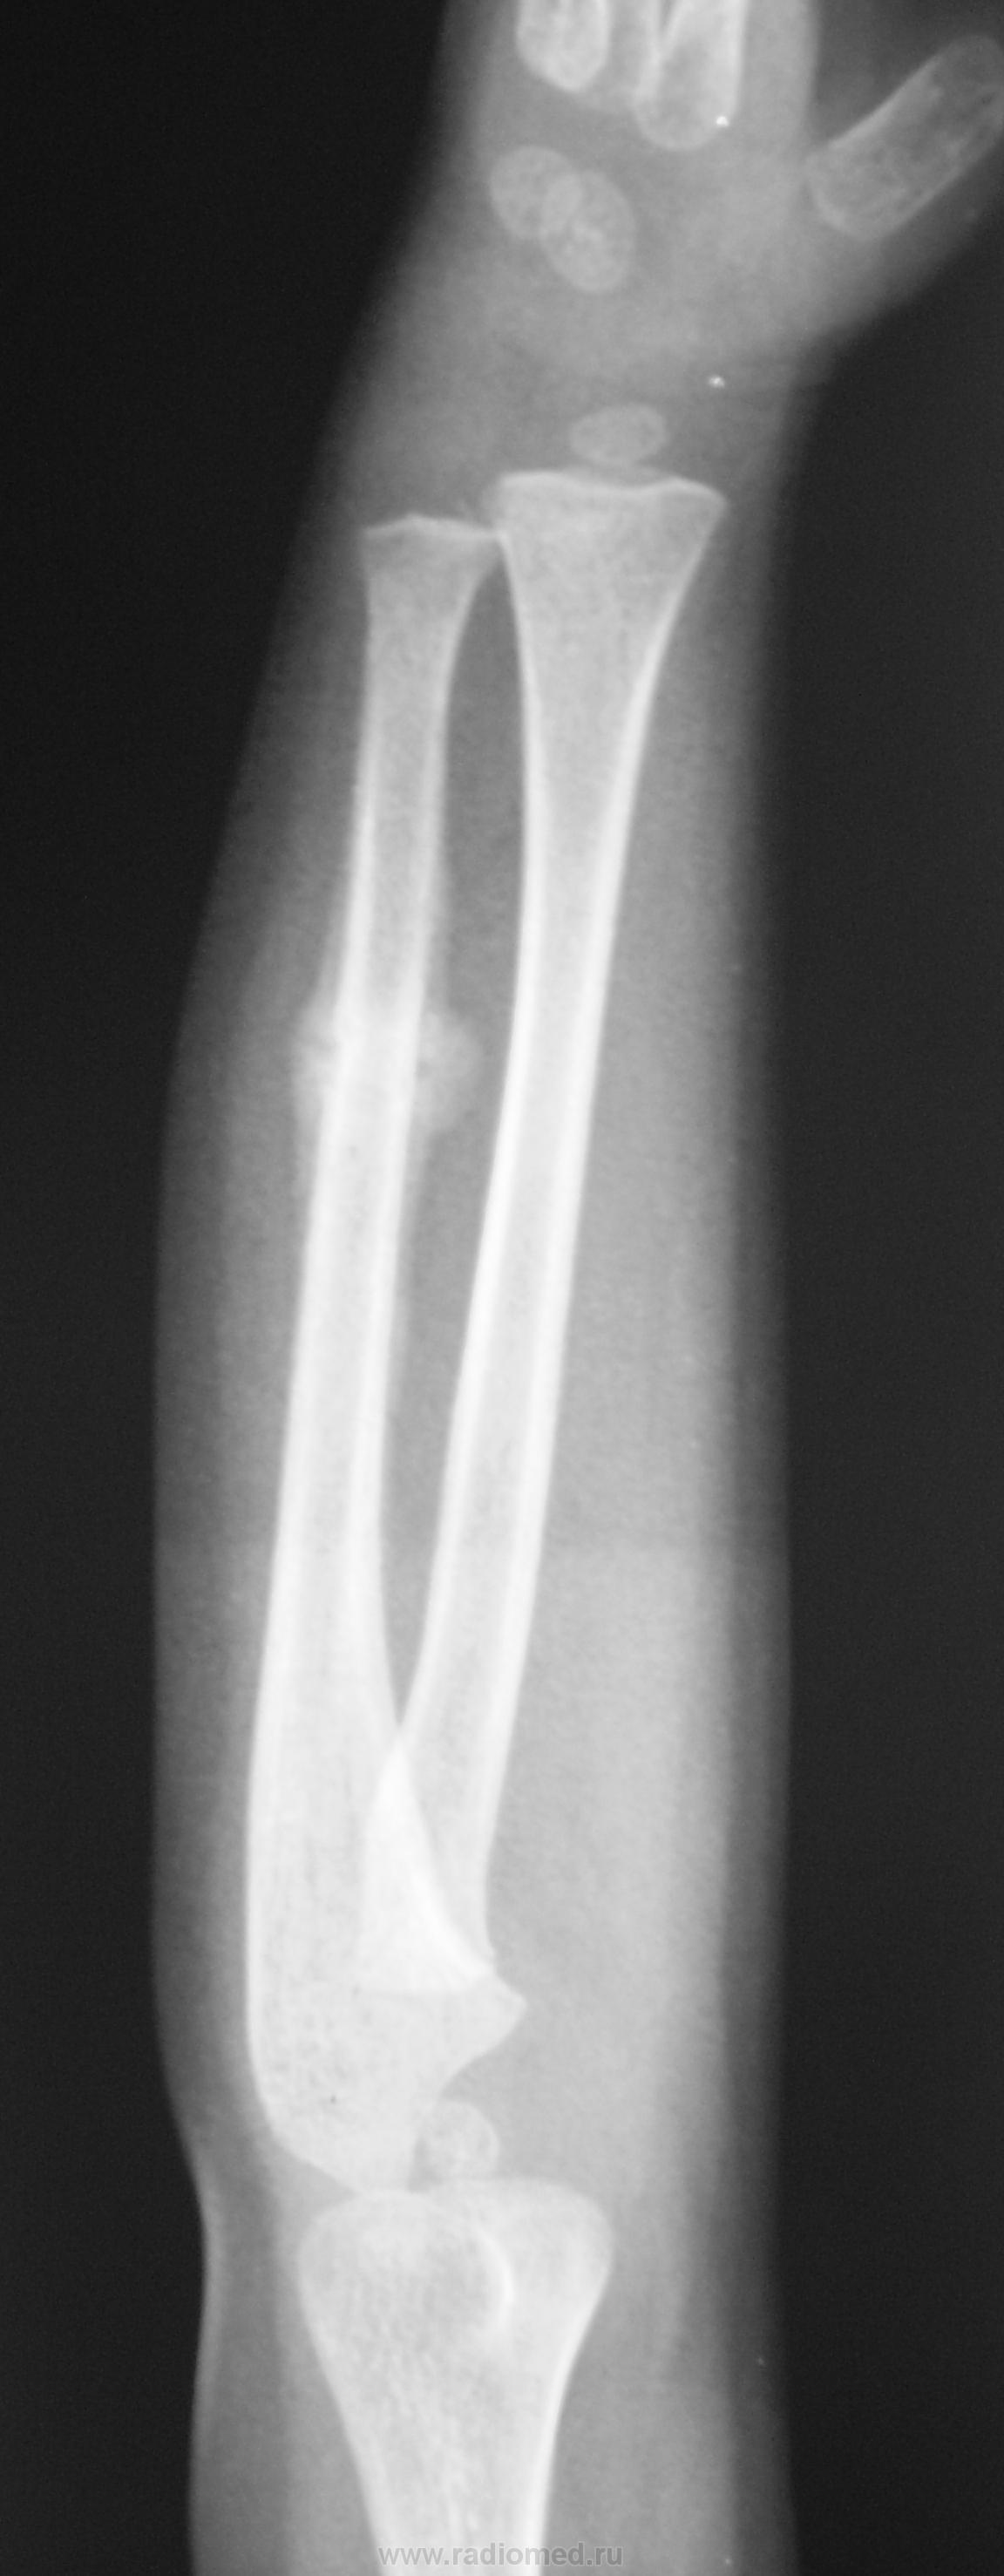

Прошел месяц после травмы...

пока консолидирующийся перелом и посттравматический периостит

Судя по снимку, ребенку около 1.5 лет. Месяца вполне хватает для полноценного сращения, что мы и имеем. Хорошая мозоль. А то что она несколько гипертрофирована - не беда. Через год и следа от перелома не останется. Нормальное течение.